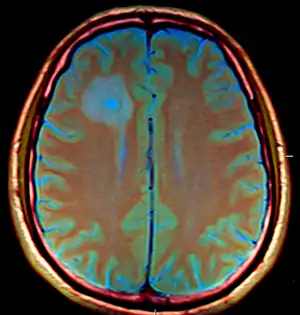

Cranial MRI revealed multiple, contrast-dense masses -abscesses

The CT images for the abscesses caused by Entamoeba histolytica are completely indistinguishable from the abscesses caused by any other organisms or causative agents. However, the brain abscesses are often observed in the frontal lobe or the basal ganglial regions.[6]